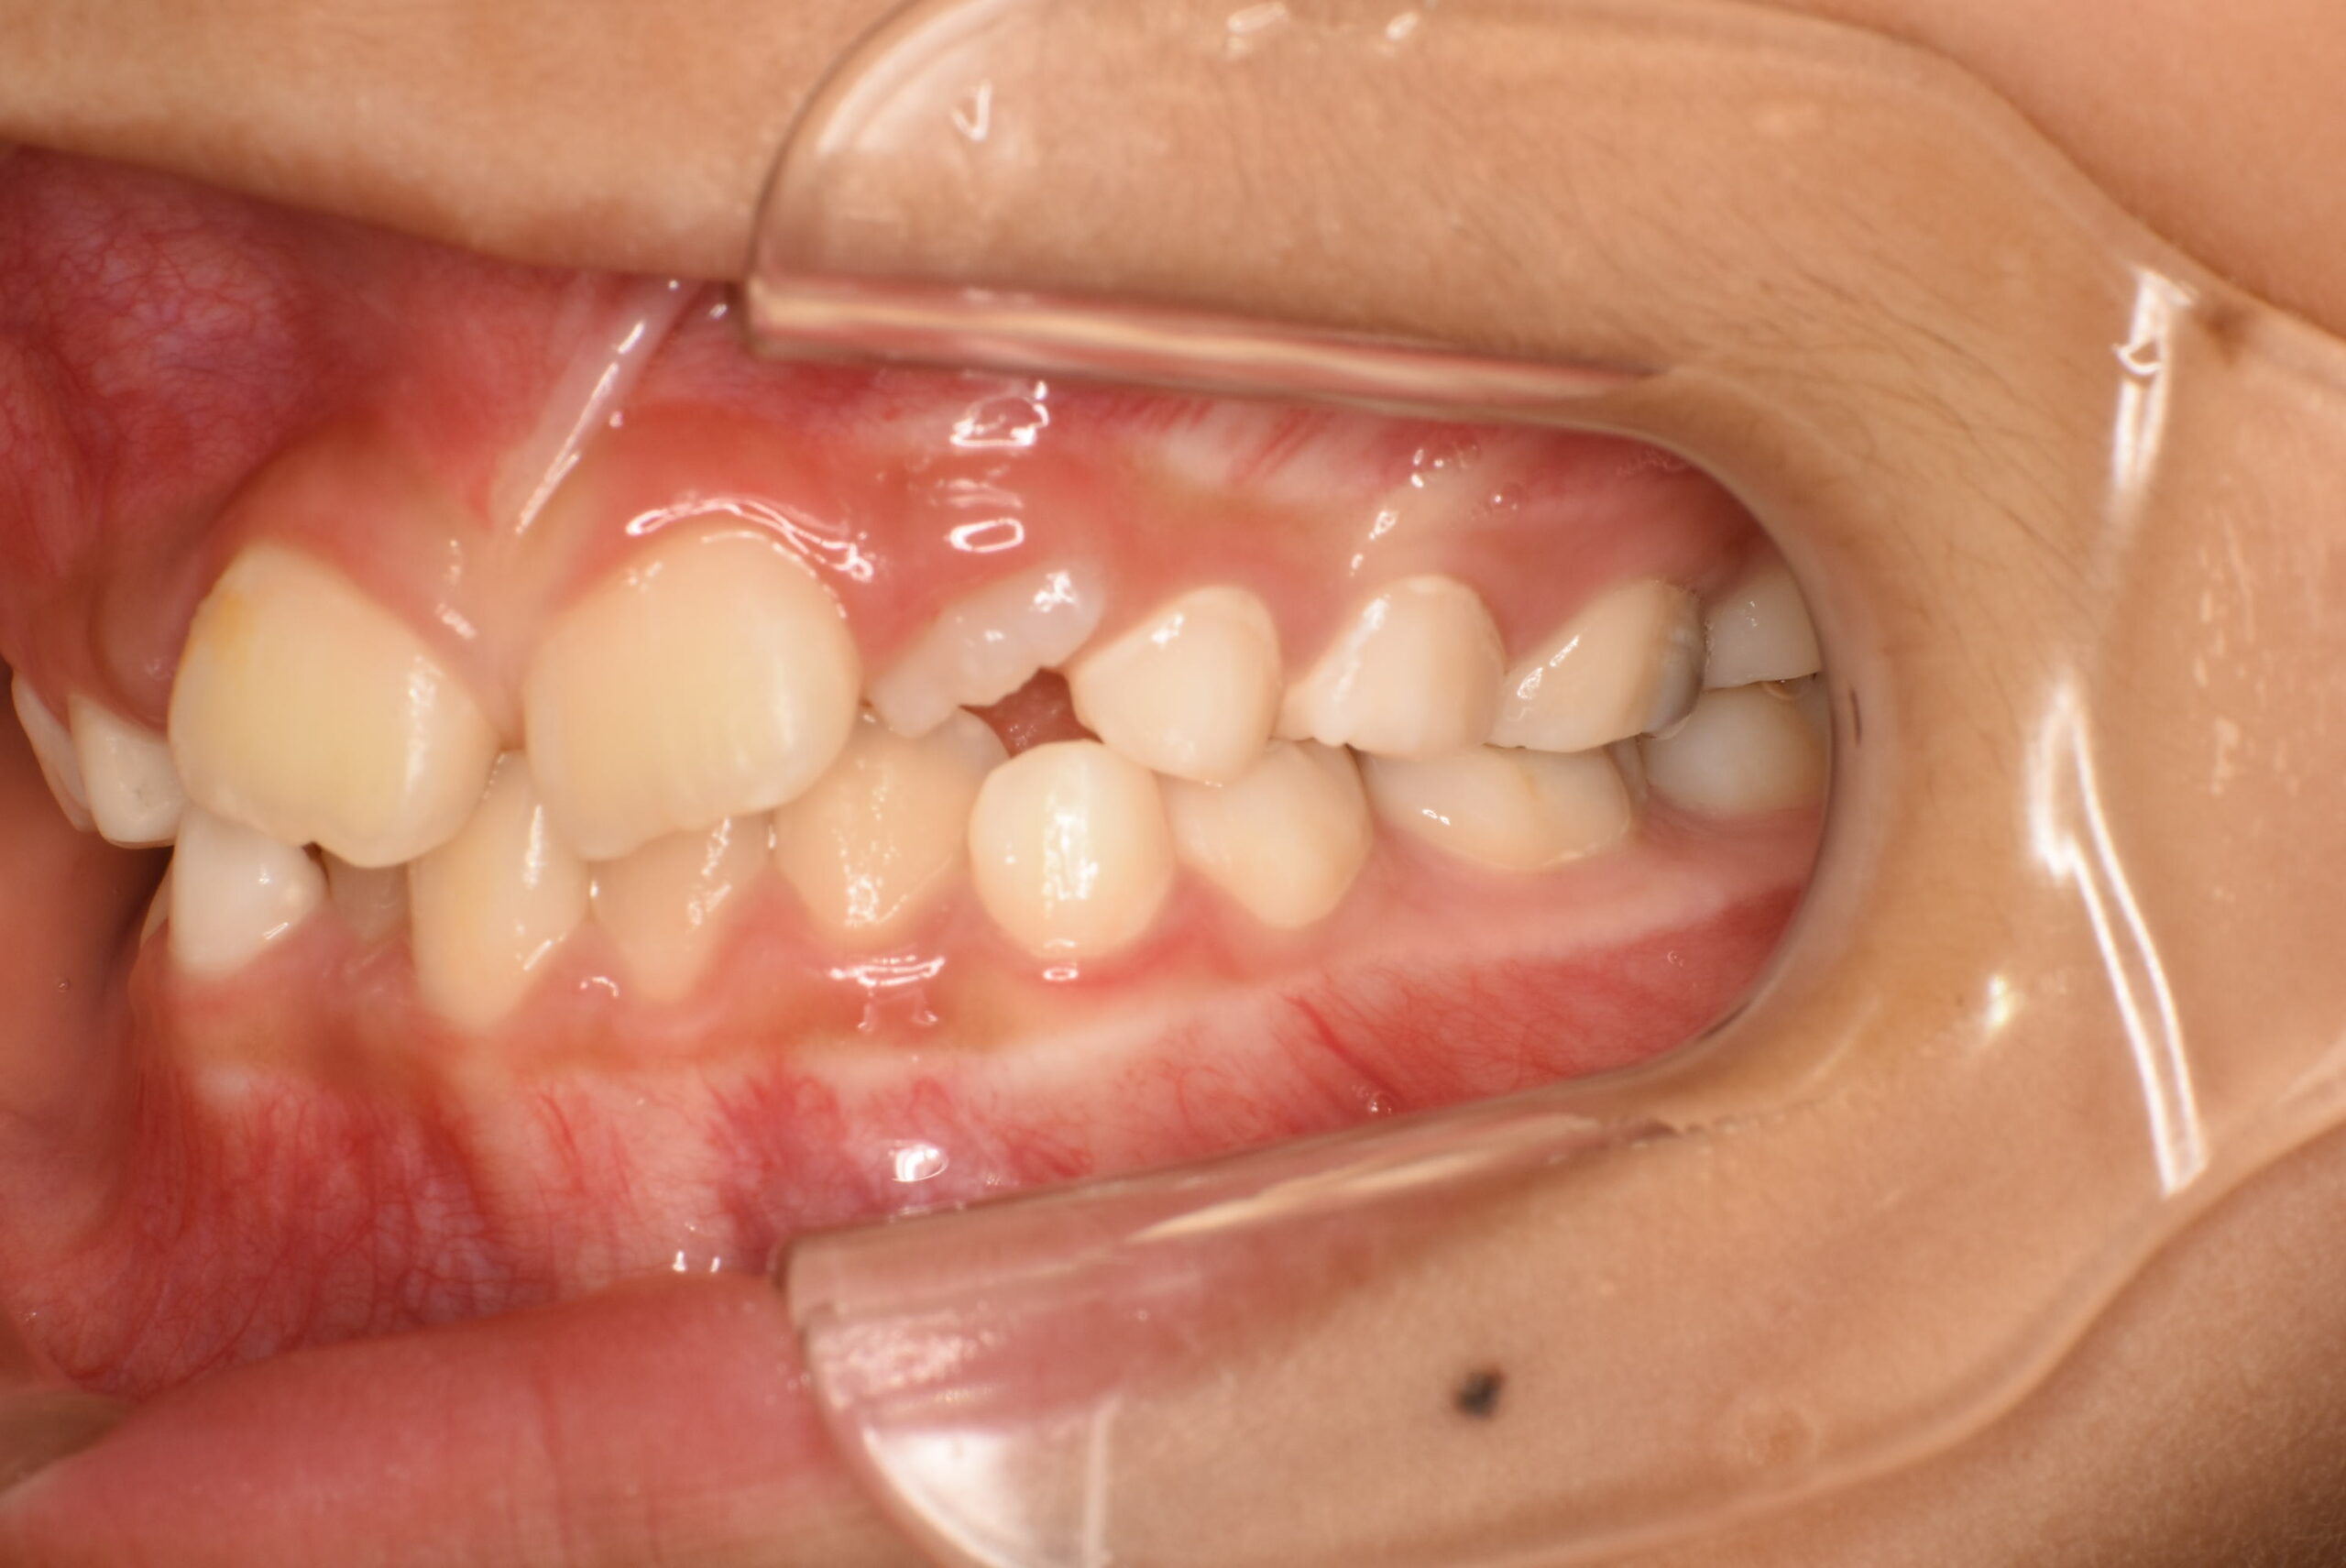

症例詳細:マイオブレースを用いた小児矯正(咬合誘導)

| 主訴 | 出っ歯 |

|---|---|

| 年齢・性別 | 女児・10歳(小学4年生) |

| 診断名 | 上顎前突(出っ歯)、口呼吸および舌の癖 |

| 治療内容 | 日中1時間と就寝時のマウスピース装着に加え、呼吸・舌・飲み込み・唇を鍛えるトレーニング(アクティビティ)を毎日実施。 |

| 治療期間 | 2年2か月(現在も継続中) |

| 費用(税込) | 583,000円 ※検査代・装置代・月1回調整料5,500円含む |

| リスク・副作用 |

|

| 備考 | 本症例は治療途中の経過写真です。治療結果には個人差があります。 |